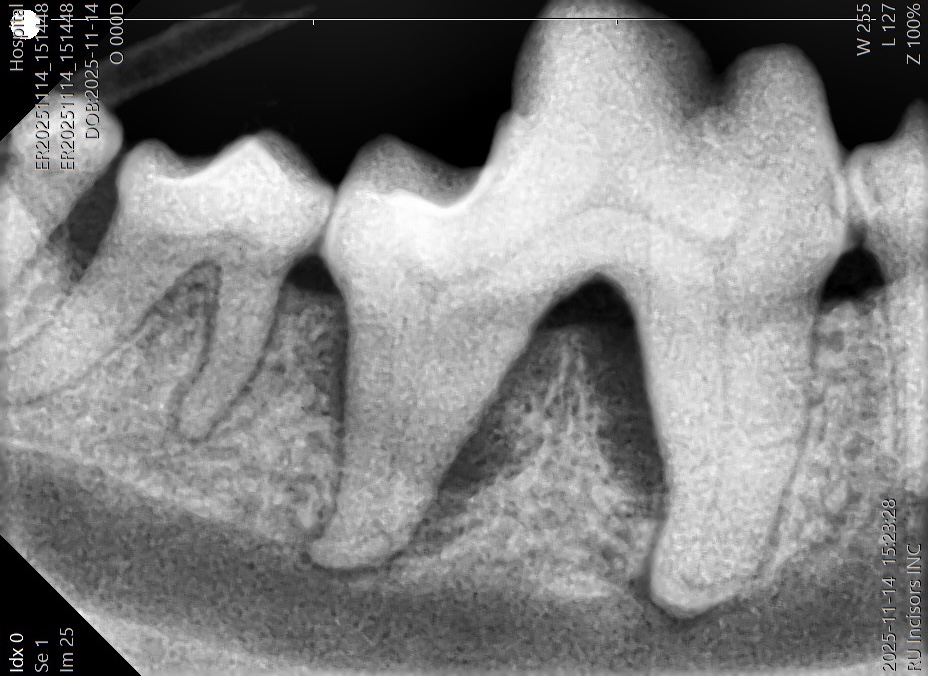

歯科用レントゲンによる精密診断

当院では、歯科診療専用のレントゲン装置を使用し、詳細な画像診断を行っています。一般的なレントゲンと比較して、歯や歯槽骨の状態をより鮮明に把握できるため、診断の精度向上につながります。これらの画像診断機器を活用し、病態を正確に評価したうえで最適な治療をご提案します。

重度歯周病に伴う歯槽骨吸収